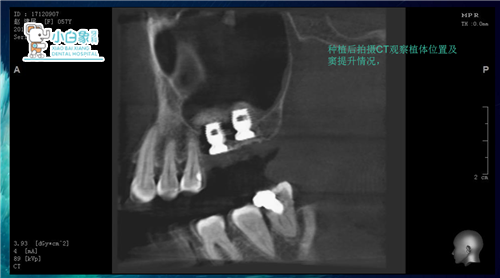

治疗过程:16局麻下切龈翻瓣,内提升后置骨粉植入百康5*6植体一枚,严缝合。

17局麻下拔除,清理拔牙窝后内提升置骨粉植入百康5*6植体一枚,严密缝合。